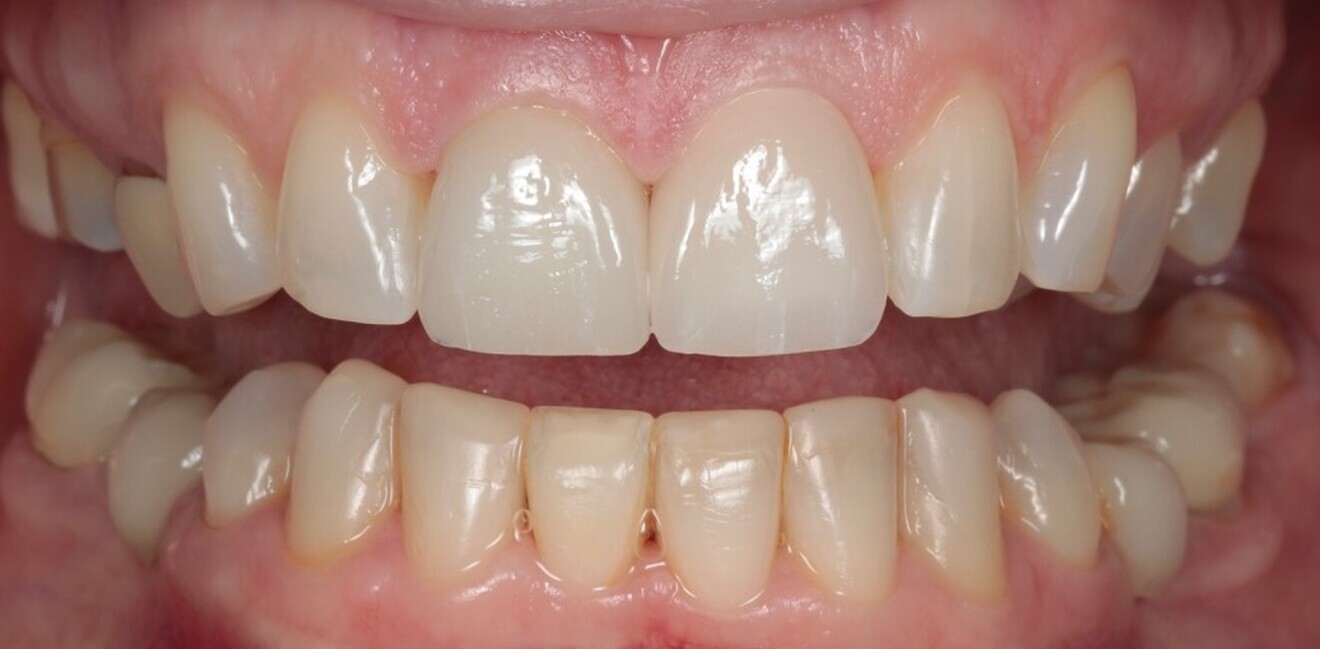

In 2021, the patient decided to have the two maxillary central incisor restorations replaced with a lithium disilicate crown and veneer (Fig. 13). The maxillary palatal platforms created with Venus Diamond in 2017 were still functional, and the repaired mandibular central incisal edge was still intact (Figs. 14 & 15). The original edge bonding on the other mandibular teeth still remained in place, 17 years later.

Fig. 13: 2021—the two maxillary central incisor restorations replaced with a lithium disilicate crown and veneer.

Fig. 16: 2021—the patient’s teeth 17 years later thanks to interceptive treatment with alignment and direct edge bonding according to the Dahl principle to minimise the amount of damage.